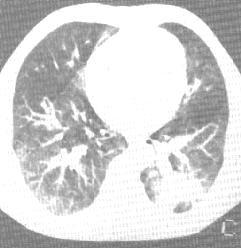

2、CT表現:

(1)氣管、主支氣管和葉支氣管腺瘤表現為管腔內結節狀腫塊,邊緣光滑。有壁外延伸時可並存管腔外腫塊。病變遠側常有阻塞性肺炎或肺不張。

(2)外圍型腺瘤表現為肺內軟組織密度結節,邊緣光滑。

支氣管腺瘤 X線表現 | 支氣管腺瘤 CT表現 | 支氣管腺瘤 CT表現 |